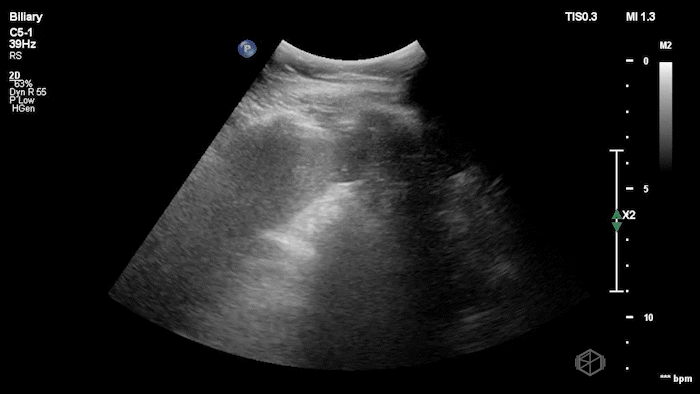

Dr. Mendelow was scanning a late 20’s male with acute epigastric and right upper quadrant pain with nausea and vomiting. He was significantly hypertensive and tachycardic likely due to pain. On exam the patient had a notable Murphy’s sign.

Dr. Mendelow performed a POCUS within 5 minutes that showed the following:

This scan shows a gallbladder filled with stones as indicated by the bright hyperechoic stones with shadowing posteriorly and almost no visible gallbladder wall lumen. This is consistent with a Wall-Echo-Shadow (WES) sign or configuration. The patient had a significantly elevated lipase and total bilirubin indicating gallstone pancreatitis. Radiology ultrasound resulted 90 minutes later with similar findings.

Diagnosis: Gallstone pancreatitis; WES sign